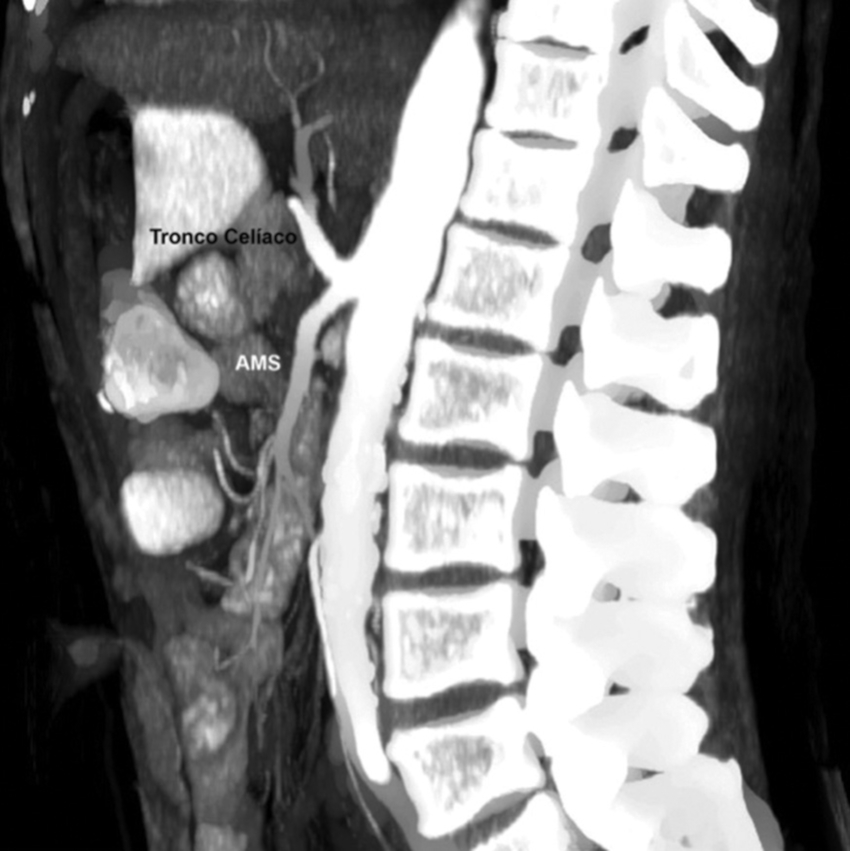

El tronco celíaco o arteria celíaca emerge de la cara ventral de la aorta abdominal después de cruzar el hiato aórtico diafragmático (a nivel de los cuerpos vertebrales D12 y L1), y luego de un trayecto de 10 a 15 mm se divide en tres ramas terminales: la arteria gástrica izquierda (AGI), la arteria hepática común (AHC) y la arteria esplénica (AEsp) (9,10.

Tipo 9: la AHC emerge de la AMS (Fig. 17).

Además, se observaron variantes fuera de la clasificación de Michels en 6 casos (2.2%): ausencia del tronco celíaco en 3 casos, tronco celíaco mesentérico en 2 casos (Fig. 18), y arterias hepáticas aberrantes derecha e izquierda originarias de AMS en 1 caso. Asimismo, en 3 casos de la variante tipo 1 de Michels se observaron los hallazgos asociados del arco de Bühler (Fig. 19).